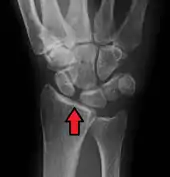

X-ray images indicate scapholunate ligament instability when the scapholunate distance is more than 3 mm, which is called scapholunate dissociation.[7] A static scapholunate instability is generally readily visible, but a dynamic scapholunate instability can only be seen radiographically in certain wrist positions or under certain loading conditions, such as when clenching the wrist, or loading the wrist in ulnar deviation.[6]

In order to diagnose a SLAC wrist you need a posterior anterior (PA) view X-ray, a lateral view X-ray and a fist view X-ray.[8] The fist X-ray is often made if there is no convincing Terry Thomas sign. A fist X-ray of a scapholunate ligament rupture will show a descending capitate bone. Making a fist will give pressure at the capitate, which will descend if there is a rupture in the scapholunate ligament.

Static scapholunate dissociation

Scapholunate ligament disruption associated with a Colles' fracture